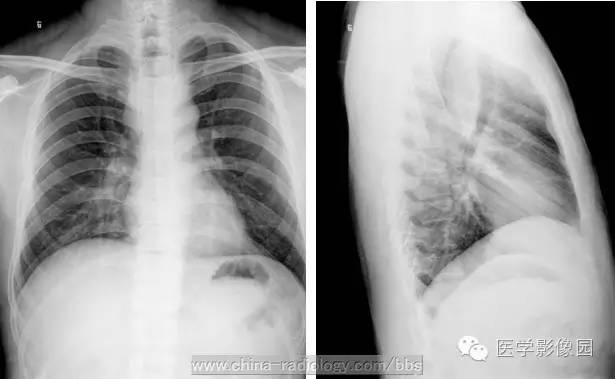

X线食管钡餐检查是本病的主要诊断方法,结合临床表现,往往可以一次造影确诊。

钡餐造曩所见取决于肿瘤的大小形态和生长方式。腔内充盈缺损是主要表现,缺损呈圆形或椭圆形,边缘光滑锐利,与正常食管分界清楚。充盈缺损上下端与正常食管交界角随肿瘤突入管腔多少而呈锐角或轻度钝角。正位时与食管长轴垂直的肿瘤轮廓由于钡餐的对比显示为半圆形阴影,出现“环形征”。肿瘤处粘膜被顶出,皱襞消失,该处钡剂较周围少,成一薄层,形成“瀑布征”或“涂抹征”。肿瘤大的在充盈缺损所在部位可见软组织阴影,透视下观察钡剂通过情况,在肿物上方稍停一下,然后在肿瘤与对侧食管壁间呈带状通过,状如小沟。肿瘤附近的食管壁柔软,收缩良好,近端食管不扩张。

多发性平滑肌瘤或马蹄形肿物环抱食管,使管腔凹凸不平,粘膜显示不清,要注意与食管癌的鉴别。后者管壁僵硬,充盈缺损不规则,有粘膜破坏及龛影等。

食管平滑肌瘤与纵隔肿瘤处压改变的不同在于:后者管壁处充盈缺损较浅,切线位肿物与管壁间的钡影成钝角,食管双侧壁同时向一侧偏移。